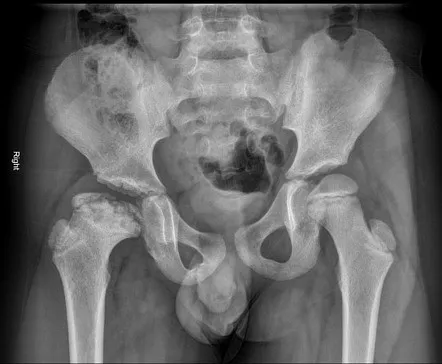

Çocuklarda topallama ve kalça ağrısı ile giden hastalıklarla ayırıcı tanıya gidilmelidir. Çoğu zaman yaş, cinsiyet ve bulguların süresinin değerlendirilmesi, iyi bir fizik muayene ve radyolojik tetkik ile ayırıcı tanıya gidilebilir. Hastalığın tanısında öykü, fizik muayene ve görüntüleme yöntemleri kullanılmaktadır. Özellikle erken dönemde röntgende değişiklikler meydana gelmeden MR görüntüleme erken tanıda çok yardımcıdır, ileri dönemde röntgenle tanı rahatlıkla koyulabilmektedir. Topallayan ve ağrısı olan çocukta ortopedi ve travmatoloji hekimince muayene erken tanıda çok önemlidir. Hastalığın erken tanısı seyrini de etkilemektedir.

Femur başının yeniden şekillenmesi (remodellingi) özellikle Perthes hastalığından etkilenen yaş grubunda hızlı olduğu için femur başının örtümünü sağlayan cerrahi dışı ve cerrahi tedaviler tedavinin ana prensibini oluşturmaktadır. Tedavide asıl amaç beslenmesi bozulan femur başının yeniden şekillenmesinin ve kalça eklem yuvası (asetabulum) ile uyumlu olmasını sağlamak ve kötü sonuçla ilişkili femur başı şekil bozukluğunu önlemektir.